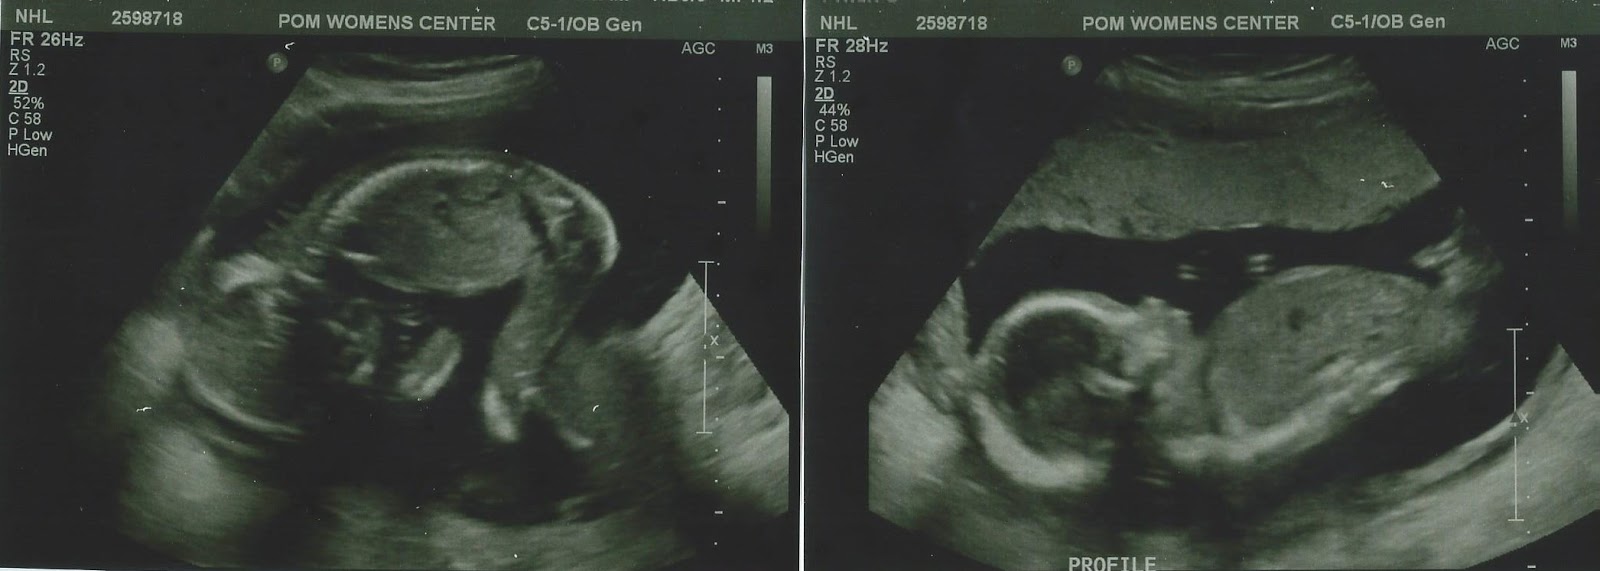

It's a baby girl! 超音波照片裡的寶寶很可愛,醫生說眼睛很大 很好動 還會後空翻。隨著音音愛臨逐漸長大,每次看著她們手足情深的樣子,就會想說兩個是不是太少了,三個應該在成長過程更可以彼此照顧。